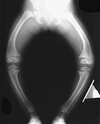

A 12-month-old boy has right congenital fibular intercalary hemimelia with a normal contralateral limb. A radiograph of the lower extremities shows a limb-length discrepancy of 2 cm. All of the shortening is in the right tibia. Assuming that no treatment is rendered prior to skeletal maturity, the limb-length discrepancy will most likely

Many congenital limb deficiencies and bowing deformities result in growth retardation. If unilateral, a gradually progressive limb-length discrepancy will result; however, the proportional lengths of the lower extremities will remain at a relatively constant ratio. For example, if the right foot is at the level of the left knee at birth, this will still be true at maturity. This concept can be useful for early prediction of limb-length discrepancy by using a “multiplier method,” as described by Paley and associates. This method can facilitate early treatment decisions, such as the need for amputation, without having to wait for serial scanography measurements.